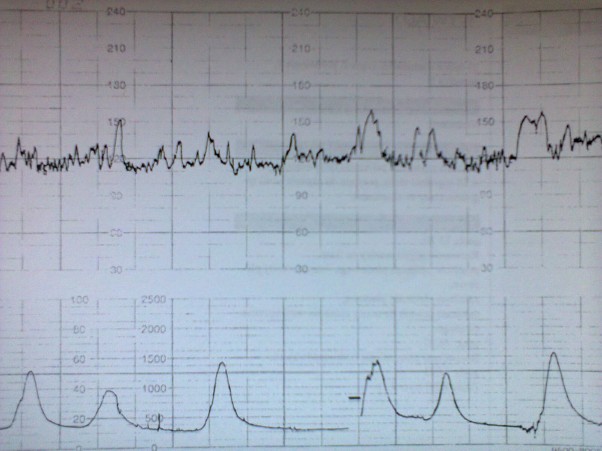

KTG

Badanie KTG musiałam wykonać w szpitalu, Eliza podczas badania spała.